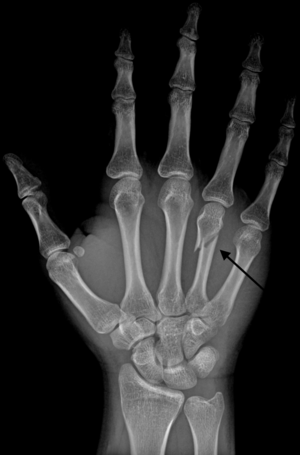

DP (PA) right hand x-ray showing fracture at the neck of fourth metacarpal bone | |

Boxer's Fracture is a colloquial term for a fracture of one of the metacarpal bones of the hand. Classically, the fracture occurs transversely across the neck of the bone, after the patient strikes an object with a closed fist. Alternate terms include scrapper's fracture or bar room fracture.

Diagnosis by a doctor’s examination is the most common, often confirmed by x-rays. X-ray is used to display the fracture and the angulations of the fracture. A CT scan may be done in very rare cases to provide a more detailed picture.